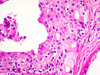

CASO N° 2 (Dr. Elismauro e Dr. Delgado)

Paciente do gênero masculino, 85 anos de idade, apresenta um aumento de volume na maxila esquerda.